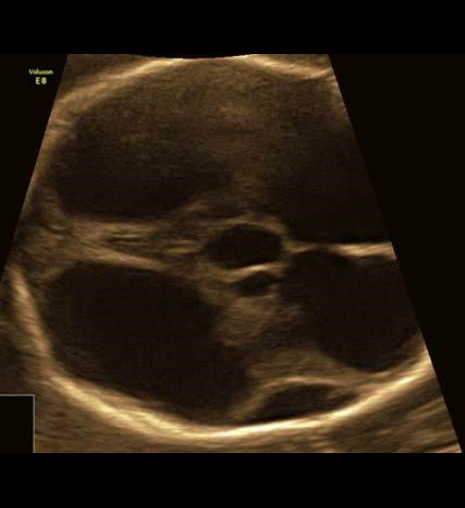

Вопрос 4

Срок 22 недели 5 дней. Вентрикуломегалия тяжелой степени. Пол плода — женский. В какой части головного мозга скрывается основной диагноз?

Трансцеребеллярный скан и 3Д режимы

Ответ на вопрос 4

- Поиск основного диагноза нужно вести в области задней черепной ямки (смотрим НАЗАД).

- Очевидно, что полушария мозжечка уменьшены в размерах (фокальная гипоплазия полушарий мозжечка), червь сформирован правильно (об этом подробно поговорим на второй лекции).

- При консультировании — обязательно предлагаем инвазивную диагностику с лабораторным исследованием молекулярного кариотипа (ХММА).